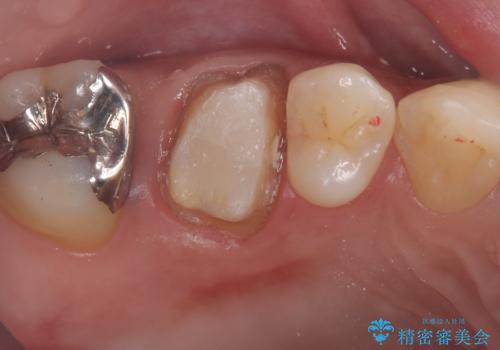

メタルクラウンを除去したところ近心面に大きな窪みとう蝕を認め、ファイバ-コアからのやり替えとしました。クラウンは審美性の良いセラミッククラウンを選択されました。